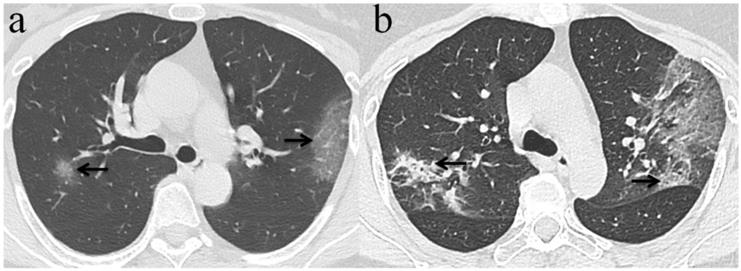

Figure 5

Evolution of chest CT imaging findings in a 30-year-old female patient presenting with fever (range:38.1-39℃), cough and expectoration for four days. (a)6 days after initial symptoms, subpleural GGO with partial consolidation was presented in the left lower lobe(black arrow).While, the patient's initial RT-PCR was negative; (b) day 11, there was an enlarged region of GGO and consolidation(black arrow),and was demonstrated new GGO appeared in other lesions of left lobe(white arrows).One day later, swab test turned positive for SARS-CoV-2; (c) day 16, the overall range of lesions was smaller than that of day 11, but the subpleural consolidation were more frequent(black arrow);(d) day 22, continued resolution with consolidation(black arrow) and other lesions of left lobe demonstrated remission.

Among the 32 patients with negative initial RT-PCR and first positive CT, only 25 patients had the second chest CT when RT-PCR test turned positive. GGO was the most frequent CT findings at the first and second chest CT [96.9% (31/32) and 84% (21/25), respectively] (Figure 3), and the right upper lobe (22/32[68.8%]) was the most commonly affected at initial chest CT scan with negative RT-PCR. Consolidation was more frequently observed on the lower lobes, and more frequently detected during the second CT (16/25[64.0%]) with positive RT-PCR than the first CT with initial negative RT-PCR (17/32[53.1%]) (Table 2, Figure 3, 4). More than two affected lung lobes were detected in 65.6% (21/32) patients at the first chest CT, and this ratio went up to 84.0% (21/25) at the second chest CT, while 12/25 (48.0%) patients had all five lobes affected. Bilateral lung involvement was more often than unilateral both at the first (22/32[68.8%]) and second (22/25[88.0%]) chest CT (Table 2). Subpleural distribution characterized the lung involvement in most patients (24/32[75.0%]) at the first chest CT, which presented in 11/25 (44%) patients at the second CT (Figure 5). However, the crazy-paving pattern is not as common at the first (4/32[12.5%]) and second (3/25[12.0%]) chest CT. No patients had cavitation, calcification, or lymphadenopathy.

The median total lung severity score was 6 in the initial CT examination and 8 in the second chest CT (Table 2, Figure 6). Noticeably, 13/25 (52%) patients progressed mildly, 8/25 (32%) patients demonstrated remission, and the other 4/25 (16%) patients remained unchanged appearance in the second chest CT.